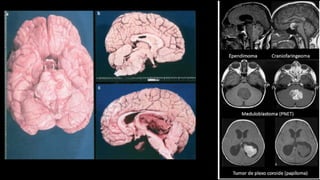

🡪 Causas: - A) Estruturais (1/3)

A) Causas Estruturais

1) Lesão direta no TE (AVC, dça desmielinizante):

2) Lesões focais, com grande efeito de massa HIC

Hérnias Compressão TE

3) Condições que comprometam encéfalo globalmente

2) Lesões focais com efeito de massa

❑ Com aumento de PIC 🡪 Herniação

Hérnias

• Passagem de tecido encefálico para compartimentos que

normalmente não ocupariam.

• Principais causas: AVCs, tumores, TCE, Lesões expansivas, etc

• Tipos:

- Subfalcina (giro cíngulo por baixo da foice do cérebro)

- Uncal (úncus através do tentório, para fossa

posterior) 🡪 Acometimeno NC III

- Tonsilar (amigdala cerebelar pelo forame magno) 🡪

compressão bulbar

- Central (diencéfalo para baixo) 🡪 compressão

mesencefálica

I-Lesão Supratentorial: Neoplasias, AVC, lesoes extensas 🡪 Herniação

CAUSA: I - Estrutural Supratentorial

• Neoplasia:

CAUSA: II - Estrutural Infratentorial

• Neoplasias do Tronco Encefálico e Cerebelo